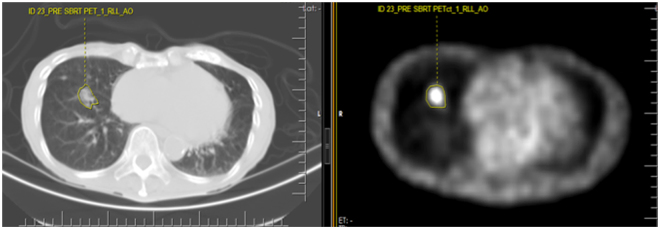

Figure 6.

Screenshot of the texture analysis software applied on a staging PET/CT study for a NSCLC patient before SBRT therapy. On the left is the CT image and on the right, is the PET image of the PET/CT at the exact same level. The manual contouring of the right lower lobe tumor on both images is noted. There was an event of distant metastasis and death. SUVmax = 1.9. The significantly low SUVmax failed to predict the poor clinical outcome as evidenced by the development of distant metastasis and ultimately death.

The CT and CT corrected attenuated PET images were transferred to a dedicated research computer for further textural feature analysis with ProCanVAS (Prostate Cancer Visualization and Analysis System), a computer aided imaging diagnosis tool developed in our department. Preliminary image thresholding was performed to exclude air, fat tissue and calcifications, i.e. pixels with attenuation values <−50 HU and >300 HU were excluded. Manual contouring was performed on the lesion of interest separately on the CT and PET images of the pre-treatment PET/CT studies. The delineation of the tumors was performed manually by a thoracic radiologist (A.O.) with 14 years of experience in thoracic imaging and 2 years of experience in texture analysis of lung cancer with the help of a 3rd year medical student (U.T.) involved in the research project. Each lesion was contoured on every sequential slice that was visible on CT as increased homogeneous or ground glass density compared to surrounding normal lung parenchyma. Attention was made so that volume averaging areas, adjacent vascular structures were not included in the regions of interest. The segmentation/contouring of the lesions on the PET images was performed manually on all the sequential images showing increased FDG uptake in the corresponding area of the tumor, which was either the same area covered on the equivalent CT images or slightly smaller. The texture features were calculated for each separate slice (Figs 6 and 7) on the PET and CT images.